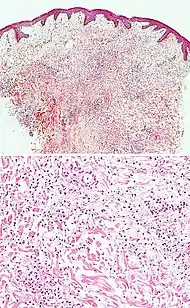

Cutaneous small-vessel vasculitis

• Neutrophils with nuclear dust (dashed arrows in image), with high affinity for postcapillary venules.[28]

• Features of vascular injury: fibrinoid necrosis (asterisks) and erytrocyt extravasation (solid arrows)